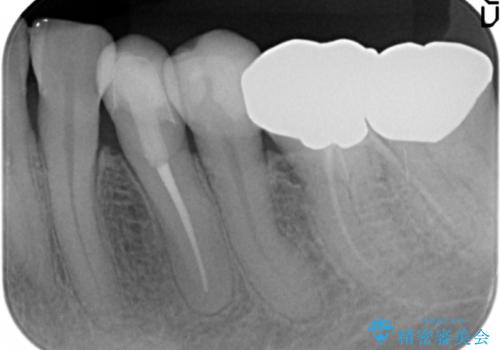

セラミッククラウンの自然な仕上がりと咬み心地に大変ご満足頂けました。

歯がしみる症状もなくなり、外側に出ていた歯が気にならなくなったと喜んで下さいました。

クラウンの種類:オールセラミッククラウン エコノミー